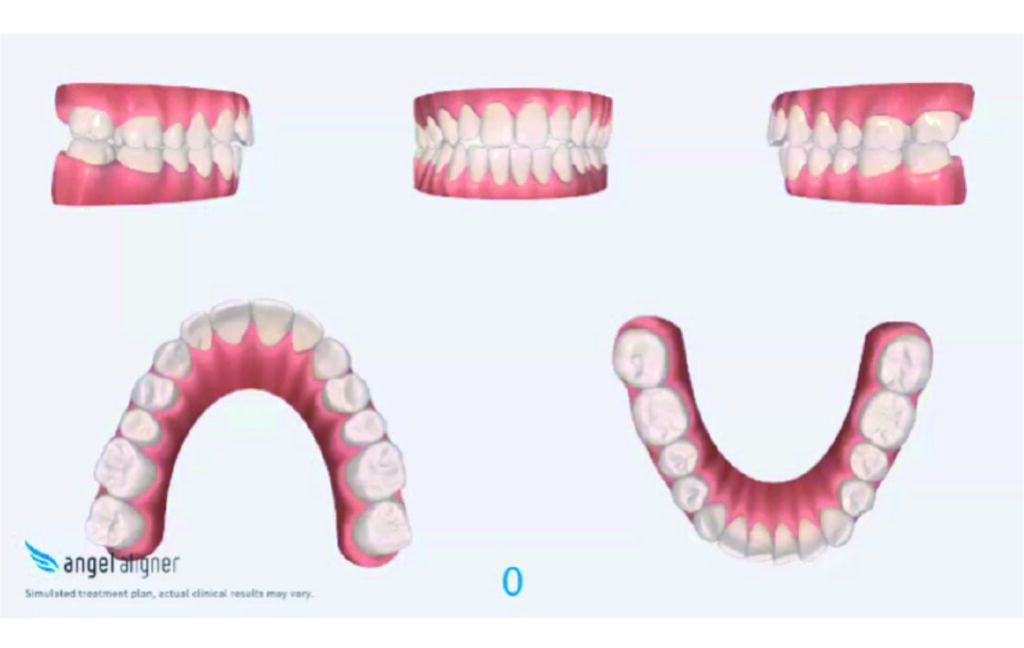

Treatment setup

Alignement and expansion 2mm per quadrant.

Distalization in segment 1 to Class I and derotation of 16, move upper central line to fit lower central line.

Derotation 26. IZC anchorage.

Settling the bite in Class I.

IPR of the lower anterior segment was performed to address Bolton discrepancy.